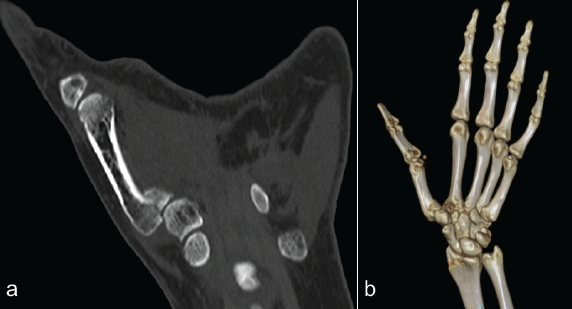

Surgery was performed under regional anesthesia with the patient in a supine position, with the left upper limb placed on an arm table. Intravenous antibiotic (injection cefuroxime 1.5 gm) was administered half an hour before tourniquet inflation. Standard preparation and draping were done. A Wagner’s incision centered over the CMC joint of the left thumb was made, and a plane was developed between the abductor pollicis longus and abductor pollicis brevis (APB). The APB and thenar muscles were raised from the joint capsule and metacarpal base. A T-shaped capsular incision was made to expose the base of the first metacarpal. Intra-articular malunion site was identified, revealing a step deformity. Osteotomy was performed at the malunion site under C-arm guidance using fine osteotomies, and the fracture was recreated. Subluxation of the metacarpal block was corrected, and the fragment was reduced anatomically (Fig. 3a, b, c).

Figure 3: (a, b and c) showing intra-operative images of the incision, osteotomy.

Reduction of the articular surface and joint surfaces was confirmed under an image intensifier (II). Provisional fixation was achieved with a 1.2 mm K wire, and reduction was confirmed under II. Definitive fixation was achieved using mini fragment screws (Synthes 1.3 mm screws: 15 mm–01, 16 mm – 01). CMC joint reduction was stabilized with a transarticular K-wire. The joint capsule was closed. We cauterized the injured palmar cutaneous nerve branch supplying the joint capsule of the basal joint lying at the thenar origin (not a planned procedure). We did not perform a complete selective neurectomy of the basal joint. Thenar origin was resutured. Incision was closed in layers, followed by an antiseptic dressing. A thumb spica plaster slab was applied with a compression dressing. Tourniquet deflated at 72 min.